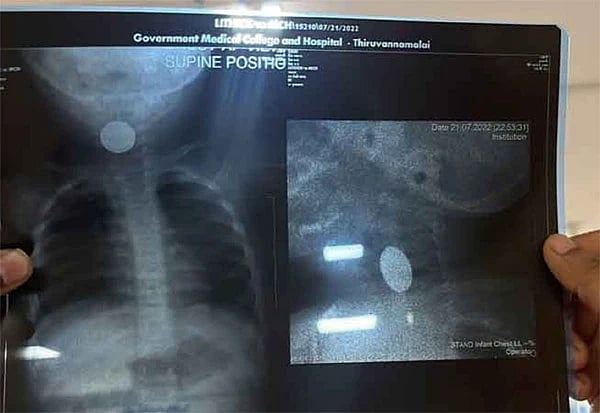

எக்ஸ்-ரே பரிசோதனை முடிவில் பேட்டரி குழந்தையின் உணவு குழாய் மற்றும் மூச்சுக்குழாய் இடையே, தொண்டையில் சிக்கியிருந்தது தெரியவந்துள்ளது. உடனே அதை ஆப்பரேஷன் இன்றி அகற்ற மருத்துவர்கள் முடிவு செய்துள்ளனர்.